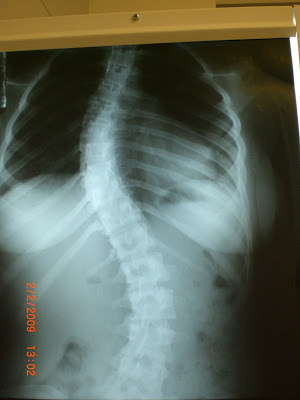

Curvatura lateral (que pende do centro para um dos lados) da coluna vertebral que pode ocorrer no segmento torácico ou lombar.

• raios X da coluna vertebral em várias posições